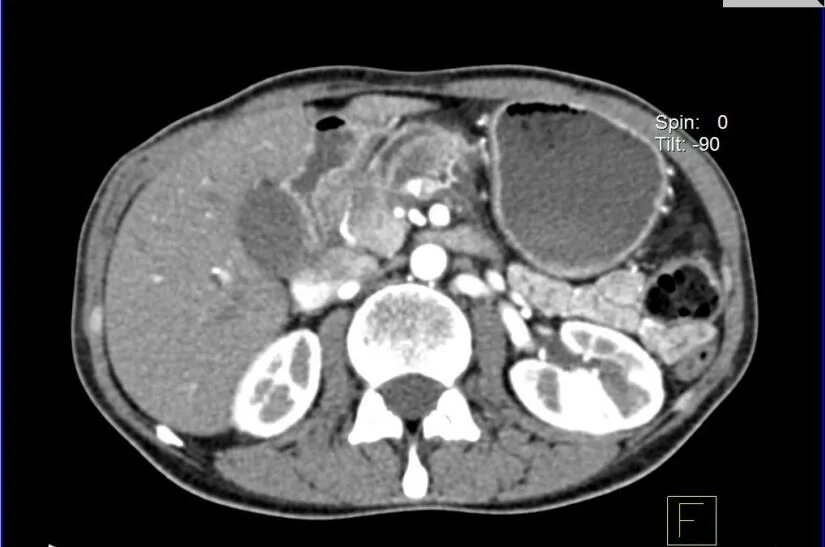

Мрт кисты поджелудочной